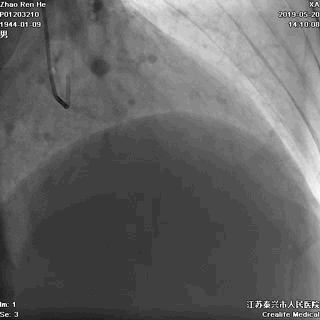

逆向途径开通RCA

1、逆向导丝抵达闭塞出口,Fielder系列引导,迅速交换CP或Gaia3导丝逆向进攻;

2、灵活使用Knucle技术;

3、前向CP或Gaia3导丝正向准备;

4、正逆向导丝交汇/无限接近;

5、Re-Cart,Kissing Wire,AGT;

6、IVUS评估和优化支架植入。